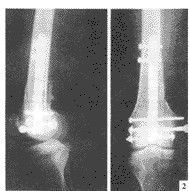

股骨幹骨折(1)股骨上1/3或中上1/3骨折多採用髓內針固定。此法具有術後不用外固定及早期下床活動的優點。過去用開放式打入髓內針的方法,近十年來已被X光電視機(XTV)控制下,僅在穿針處作小切口,不顯露骨折端的閉合穿針方法所代替。閉合法較開放損傷小,出血少,不破壞骨折端的血液供給,有利於骨折癒合。

(2)股骨中1/3或中下1/3骨折,傳統方法是採用6-8孔接骨板螺絲釘固定及髖人字石膏固定。目前多採用加壓鋼板活動。加壓鋼板有多種類型,60年代開始套用加壓器的加壓鋼板固定,其後出現自身加壓鋼板固定沿用至今。有關股骨幹骨折手術及內固定材料選擇,要嚴重掌握適應症,不可濫用。要力求手術成功,防止感染及骨折不癒合的發生。